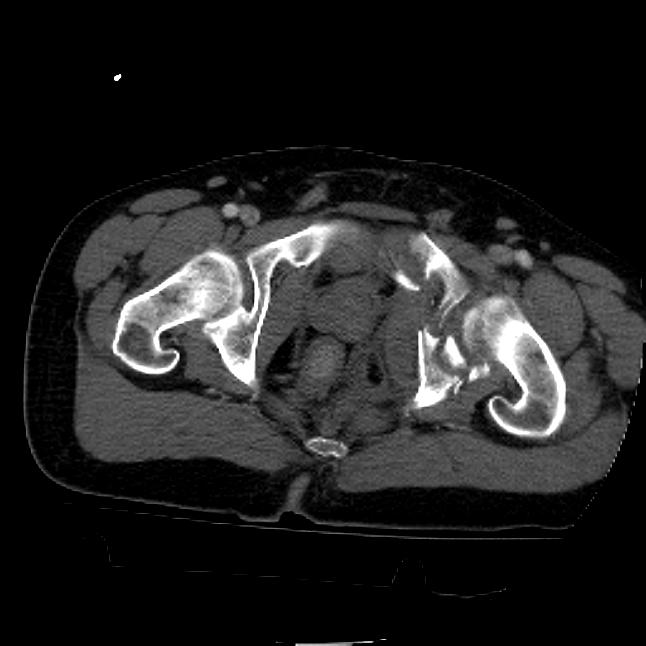

25 yo brittle diabetic, became hypoglycemic and passed out on his motorcycle. Sustained bilateral lateral Hoffa fractures with associated LCL injury on the right and right distal radius fracture. I have questions regarding his pelvic ring/acetabular fracture on the left. Appears to be a very low posterior column fracture with associated posterior wall, marginal impaction. Superior and inferior rami fractures as well on the left giving him a floating segment of inf ramus/ischium/posterior column, but no detectable posterior ring injury. Should the posterior column/posterior wall fracture be addressed surgically because of the marginal impaction? Or is this fracture low enough to be treated non-operatively? I appreciate the input.

It's an interesting case. The plain films show the impaction, but most of the joint looks pretty good. The CT cuts look awful, though.

The impaction is so big I don't think I would ignore it. It IS down low, but it takes up almost the whole southern hemisphere of his joint.